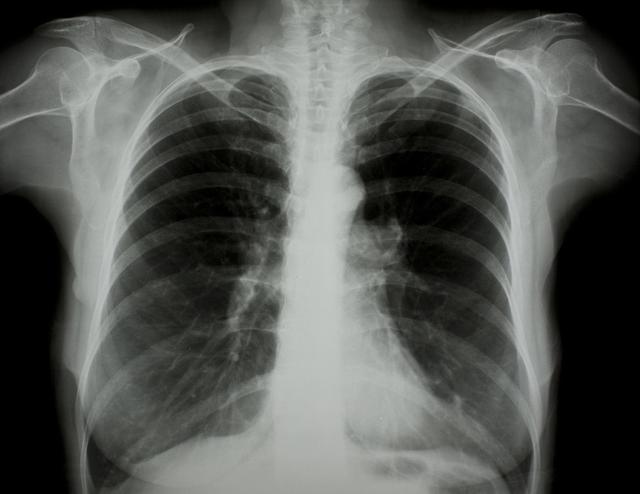

涪陵地區(qū)最新肺炎情況顯示,疫情形勢嚴(yán)峻。目前,當(dāng)?shù)卣歪t(yī)療部門正在積極應(yīng)對,采取一系列措施控制疫情傳播。具體感染人數(shù)、癥狀表現(xiàn)、疫苗接種情況等仍在持續(xù)更新中。請廣大市民密切關(guān)注官方發(fā)布的信息,做好個人防護(hù),共同抗擊疫情。涪陵地區(qū)肺炎疫情嚴(yán)峻,政府積極應(yīng)對,請市民關(guān)注官方信息,加強(qiáng)個人防護(hù)。

據(jù)最新官方數(shù)據(jù)顯示,涪陵地區(qū)肺炎病例數(shù)量令人擔(dān)憂,截至目前,涪陵地區(qū)累計確診肺炎病例XX例,疑似病例XX例,請大家務(wù)必提高警惕,不可掉以輕心。